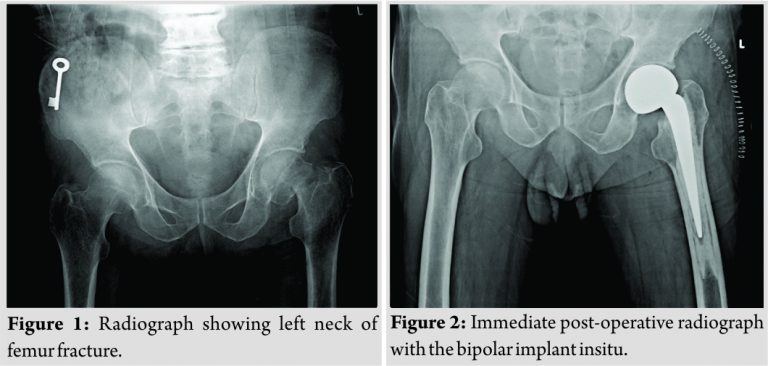

A 72-year-old male presented to the outpatient department with left-sided hip pain for1 week. The patient was a farmer by occupation and could walk with the help of a height adjustable walker upto 100 m. The patient complained of difficulty in squatting and sitting cross-legged. The pain had increased in intensity over 2 days which had affected his sleep. The patient gave no history of trauma or fall. On examination, the patient had anterior joint line tenderness with the limitation of hip movements in all the planes. Femoral pulses were well felt and bilaterally equal. Radiographic examination revealed a fracture of the left neck of the femur (Fig. 1). On further eliciting the history, the patient was diagnosed to be HIV positive 11 months back. The patient underwent left-sided total knee replacement 2 years back for which 1 unit of packed cells was given after the surgery to compensate for the intraoperative blood loss. 11 months back, the patient was planned for right-sided total knee replacement and on routine pre-operative evaluation, the patient was found to be HIV positive. The patient was started on a combination of abacavir (600 mg) + lamivudine (300 mg) with efavirenz (600 mg). The patient was compliant with the medications and would take the medications twice a day. Blood investigations sent to our institution after getting diagnosed with fracture showed no abnormality. Medical oncology opinion was taken. After all the necessary investigations and scans, no primary could be detected. Bipolar hemiarthroplasty of the hip (Fig. 2)was done since radiographically, and intraoperatively no changes were noted in the acetabulum which would have changed the plan to total hip replacement. The patient started walking full-weight bearing with a walker from the very next day after surgery. Intraoperative sample sent for biopsy was reported as Acute on Chronic Inflammatory Process with no signs suggestive of malignancy.